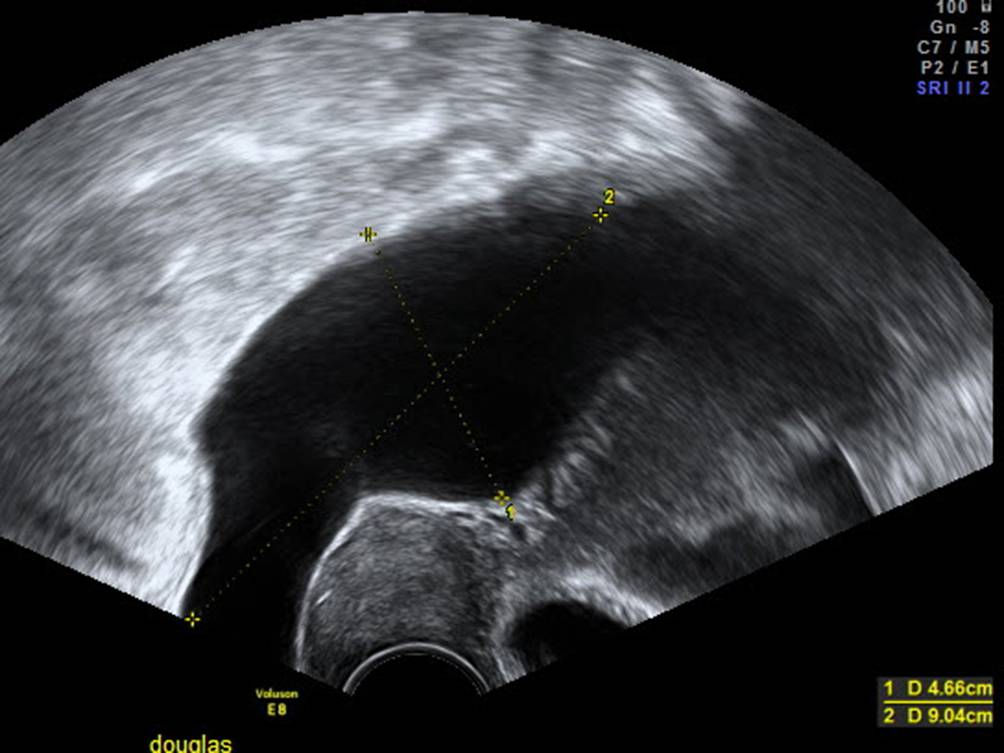

Abb. 8

Beispiel für Aszites: Dieser Befund muss in der ADNEX-Fragenliste mit „yes“ angegeben werden und führt zu einer Erhöhung des kalkulierten Risikos